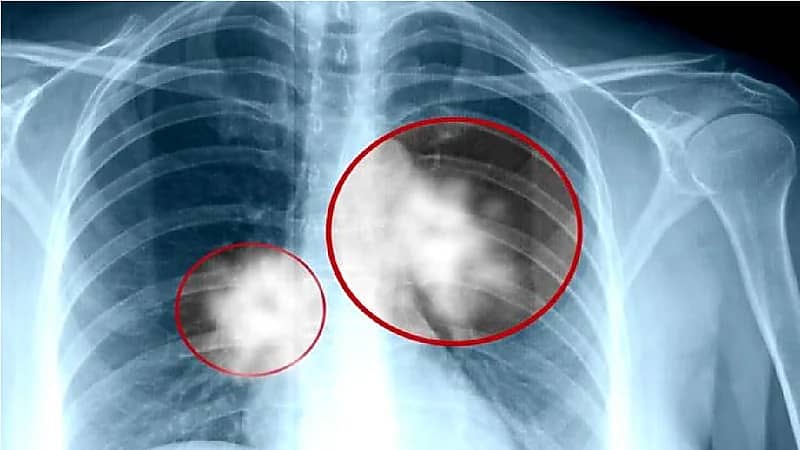

روى المواطن أحمد البدر تفاصيل رحلته مع مرض سرطان الرئة، وكيفية اكتشافه للمرض، وشعوره حينها، وما فعله للعلاج منه.

وأضاف أنه اكتشف في يوم حفل زفاف ابنته إصابته بورم خبيث في الرئة، ما جعله يشعر بشعور صعب لكنه تحمل حتى لا يفسد فرحة ابنته، وذلك وفقا لما ذكره في برنامج "يا هلا" المذاع على قناة "روتانا خليجية".

وأضاف أن الفحوصات أثبتت أن الورم انتقل من الرئة إلى المخ، وكان حجم الورم يكبر بسرعة، فلجأ إلى العلاج فتحسنت حالته لكن مؤخرًا علم بظهور ورم آخر، وبدأ رحلة العلاج منه مرة أخرى.